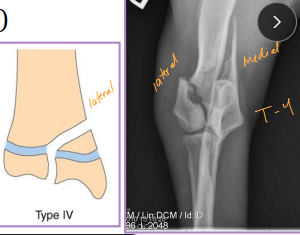

Condylar Fractures: Lateral > medial

Sig: Young dogs w/ Salter-Harris IV, older dogs w/ incomplete ossification of humeral condyle

Tx:

Lateral condyle: lag screw + anti-rotational K-wire

T or Y fracture: bilateral plates + screws